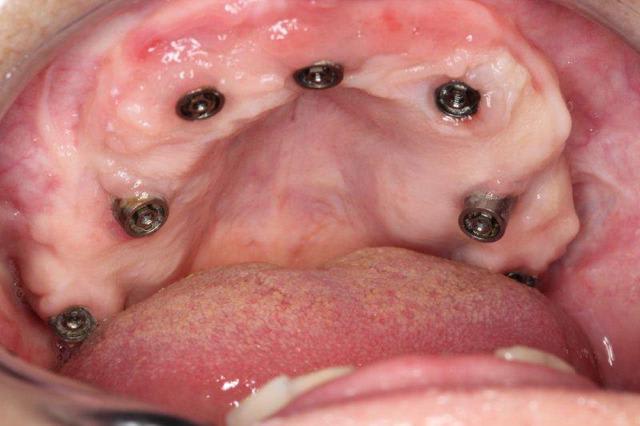

P'tite question, les vis qui tiennent la prothèse en place, sont des vis " plates", simple rainure.

L'axe de certains implants semble un peu trop palatin, mais bon, il n'y a pas de nonos...

J'aimerais voir l'hygiène dans 1-2 ans...

1. C est toi qui es malhabile... Rien de plus simple : tu mets ttes tes vis ds la puits, tu les recouvres d homéoplasmine pour les empêcher de tomber hors des puits, tu poses en bouche et tu passes ton tournevis ds homéoplasmine pour visser Très simple et très efficace :-))))

2. Effectivemeznt les plaques zygomatiques ont des émergences palatines mais au définitif j ai ôté les piliers prlongateurs de 3.5 mm et du coup même si sortie palatine plus aucun "débordement" du puits de vissage en dehors de l arcade...

3.Ca fait 18 mois que les implants sont en charge donc tu as déjà une idée mais de manière générale ça fonctionne aussi bien qu pilotis à la mandibule... Un petit coup de waterpik léger et qques bains de bouches suffisent à entretenir tout ça correctement

Regarde le provisoire de la MCI : les émergences des plaques au niveau molaires font des bombés hors arcades suite à la pose de piliers monobloc de hauteur 3.5 mm

On pose ces piliers car il faut pouvoir retrouver facilement les têtes d implants 72 h plus tard pour poser la prothèse de transition

1. l hexa te condamne à avoir un puits ds l axe exact du puits hexa... Les vis courtes et à fente te permettent de faire des puits légèrement courbe au niveau antérieur c e qui évite les vis trop gênantes vers vestibulaire qui te contraigent à faire des couronnes scellées sur armature primaire pour cacher les puits vestibulaires ...

Pp peux tu nous en dire plus sur l'aspect de la gencive qui entoure le disk le plus antérieur?

Pas le disk antérieur mais le disk et les 2 plaques antérieures pour être plus exact

La rougeur au fond du vestibule est due au frottement de la fausse gencive contre la partie libre muqueuse...

Vouspourriez dire que je suis ds la merde car la difficulté d accès à l hygiène ds cette zone a provoqué cette inflammation qui serait préjudiciable aux implants...

OUI j ai eu les boules en voyant cette muqueuse gonfler au fil des mois car j ai cru que l inflammation alllait avoir raison de mes plaques...

NON pcq la prolifération de la muqueuse n est finalement pas due au manque d hygiène possible à cet endroit mais bien au fait d avoir utilisé un matériau de comblement effciace qui donne du vrai os et sur ce vrai os on retrouve de la gencive attachée, rose, ferme, soutenue et vascularisée...gencive qui prolifère au point de comprimer la fauuse gencive et la pas la fausse gencive qui comprime la muqueuse...

Mais si j avais fait la même chose avec de l INTERPORE , matériau corralien non résorbable, non seulement je n auaris pas obtenu de l os mais alors l inflammation aurait été réelle et aurait mis en péril mon implanto...